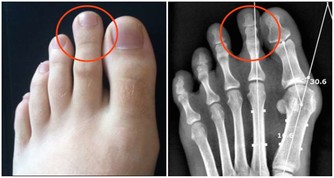

肺癌是“癌症之王”,是人類死亡的頭號殺手。肺癌的發病率男性多於女性,城市多於農村。

肺癌並非吸煙一族的專利,經常接觸二手煙、做飯的女性也是肺癌的高危人群。肺癌的致病因素比較複雜,空氣污染、環境因素、粉塵、刺激性氣味環境、遺傳史等等都是導致肺癌的致命因素,它就像一種慢性病一樣,在某種致病因素的長期刺激下,正常細胞會發生癌變,慢慢地形成腫瘤。據了解,閆懷禮在河北涿州拍攝一部叫《俏羅城》的電視劇。當地的蒼蠅、蚊子特別多,當時有一場戲拍戲的現場噴灑了很多敵敵畏,很多人都因為濃重的味道離開了,當時閆懷禮嗅覺不好感覺不到,長時間處在敵敵畏濃重的環境裡面,拍戲空擋還在那裡休息,好友六小齡童分析這是他患病的誘因之一,再加上多年拍戲工作太過勞累,閆懷禮才患上了肺癌。

肺癌幫介紹,肺癌是一種高隱藏性癌症,潛伏期最長達10年。早期沒有明顯症狀,當有的人發現腰痛、腿疼、肩痛的時候,可能肺癌已經發生了轉移,但前期沒有任何症狀。這樣的例子生活中很常見,也給我們的健康敲響了警鐘,每年定期體檢和癌症篩查是很有必要的。